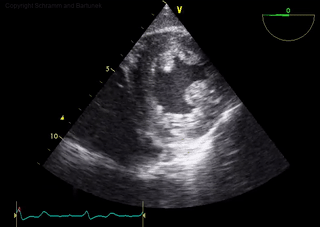

Was erkennen Sie in diesem TEE-Echokardiographie-Videoclip?